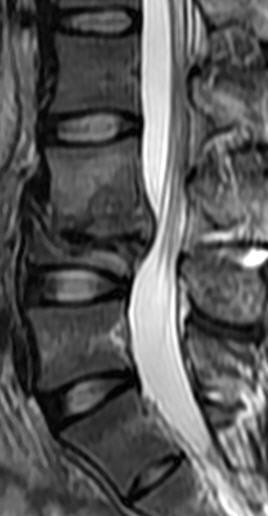

MRI

-

可提供腰椎管的矢状面、冠状面和轴位横断面上的影像。椎管狭窄以T2加权像显示较好,脑脊液为高信号,产生所谓“脊髓造影”的效果,而骨质增生,骨赘、间盘均为低信号,能清晰地显示椎管狭窄,以及对脊髓的压迫情况。但对肥大的黄韧带、骨质增生等的判断则不如较高清晰度CT扫描。

腰椎正常MRI解剖。

腰椎管狭窄MRI表现。